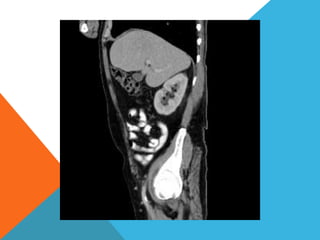

El paciente presentó síntomas de sangrado digestivo y pérdida de peso. Exámenes revelaron gastritis crónica asociada a H. pylori. Un tumor fue descubierto en una colonoscopia normal. La cirugía removió un tumor fibroide solitario, una rara neoplasia mesenquimal que usualmente crece lento y tiene bajo potencial de malignidad. El pronóstico después de la remoción quirúrgica es generalmente bueno.